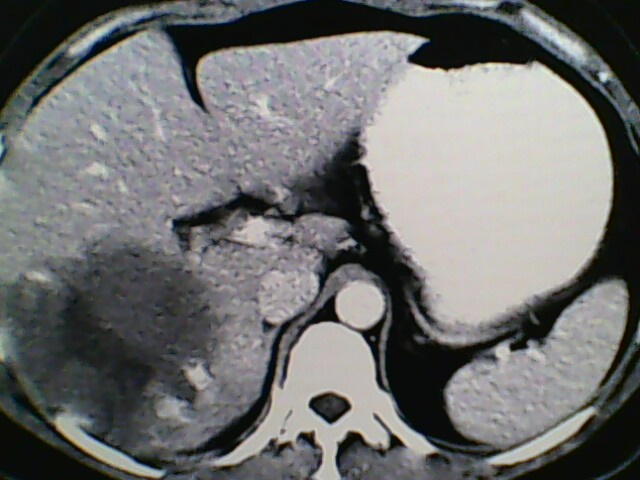

女,42岁,既往彩超检查肝血管瘤,做ct增强扫描,描述一下,依次为平扫,动脉期,门脉期,延长期

符合典型肝血管瘤强化表现

支持 肝右叶巨大肝血管瘤。

肝右叶巨大肝血管瘤。

肝右叶巨大肝血管瘤表现。